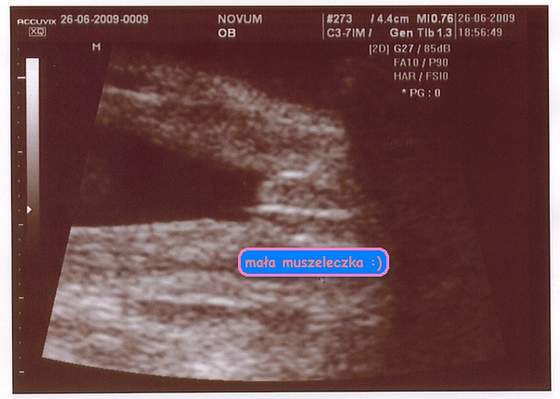

U mnie juz po połówkowym - będzie dziewuszka - tak jak chciałam tzn, tak "strzelalismy" (codziennie temperatutka, wykresik itp i się udało.Potwierdzone przez dwóch lekarzy. Pierwsze badanie mialam 19.06. w medivowerze, wczoraj kolejne robiłam prywatnie w klinice Novum - gorąco polecam, niesamowity lekarz, pokazywał, mierzył, i tłumaczył wszystkow co tylko miżliwe bswyło na tym etapie ciąży.

Mała waży 545 g , kość udowa już ma 4 cm. Niestety taka wstydliwa ta moja kobietka, że nie chciala pokazać buźki, cały czas sie zaslaniała a jak ją lekarz trochę poszturał to zacisneła piąstki, aż się śmiał ,że mała gardy przybrała i do ciosów gotowa :-) moja krew

Jak tzlko M udostepni mi skaner wkleję kilka fotek.